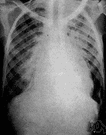

pulmonary tuberculosis

Noun1.pulmonary tuberculosis - involving the lungs with progressive wasting of the bodypulmonary tuberculosis - involving the lungs with progressive wasting of the body

Symptoms of pulmonary tuberculosis include productive, prolonged cough of three or more weeks, chest pain and hemoptysis.